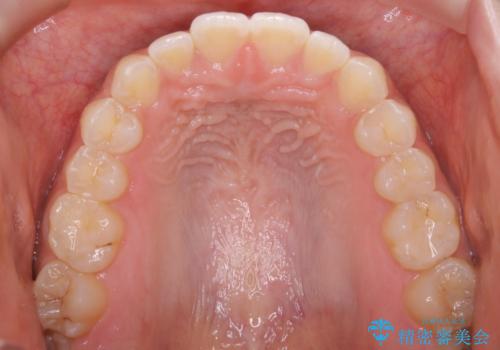

短期間ですきっ歯を改善:インビザラインLite

- 上の歯がすきっ歯なのと、歯が出ている気がするとご相談にいらした方です。

奥歯の噛み合わせに大きな問題がなく、患者様のご希望もあったため、前歯部メインで治療するインビザラインLiteで治療を行いました。

横顔のシルエットが改善し、口元もスッキリとなりました。